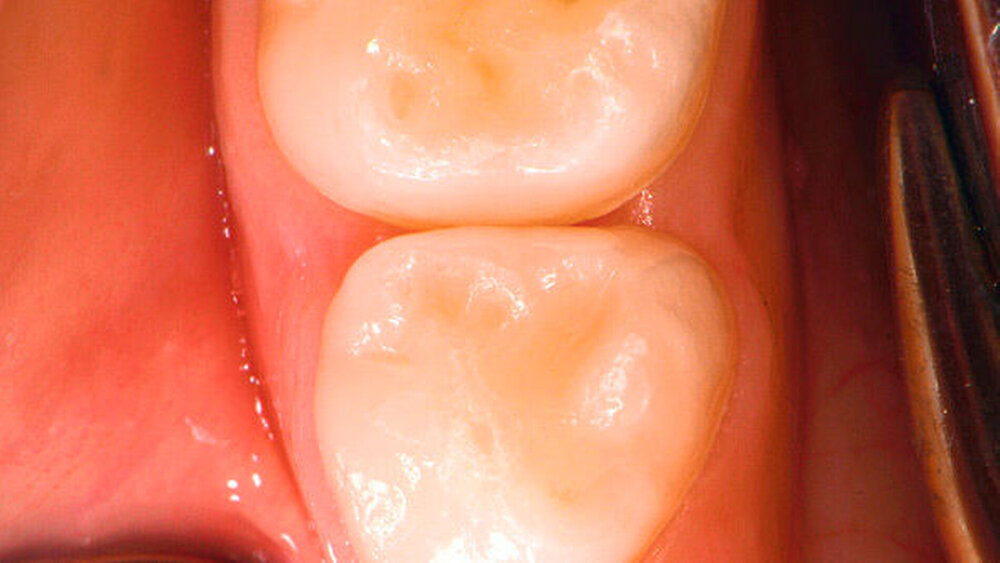

Die Approximalflächenkaries ist in ihrem frühen Stadium bei einer rein visuell-taktilen Befundung häufig für das ungeübte Auge nicht sicher zu diagnostizieren (Abbildung 1a). Die erschwerte Diagnostik ist in dem sehr tief liegenden und breitflächigen Kontaktpunkt der Milchmolaren begründet, der im unteren Drittel häufig durch die Zahnfleischpapille zusätzlich verdeckt wird [Pitts Rimmer, 1992].

Ist die Karies gut erkennbar, handelt es sich meist um kavitierte Läsionen, die mit einer pulpanahen Dentinkaries korrelieren. Nicht selten sind hier auch bereits klinische Symptome Anlass des Zahnarztbesuchs.